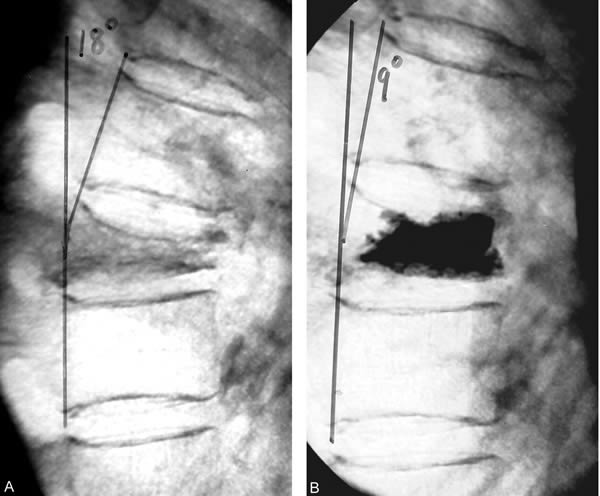

Here’s the money figure. The TRIALS line indicates quarter before publication of vertebroplasty trials in the NEJM. The AAOS line indicates quarter before release of the American Academy of Orthopaedic Surgeons statement on vertebral augmentation procedures:

Looking at the graph, it looks as though VAPS rates did decline after the studies. Indeed, as the authors reported:

The interrupted time series estimates of the effect of the trials generally confirm the observations in the figures (Table 2). Overall, the vertebroplasty rate declined by 51.5% (column 1) and the kyphoplasty rate declined by 40.0% (column 2). Both results were statistically significant (p < 0.010). Similar declines (53.8% and 38.9%; columns 3 and 4, respectively) were observed for these procedures when restricting the sample to patients with osteoporotic fractures only. The change in the vertebroplasty rate was driven by a time trend effect, while the change in kyphoplasties was driven by a level effect and a time trend effect.